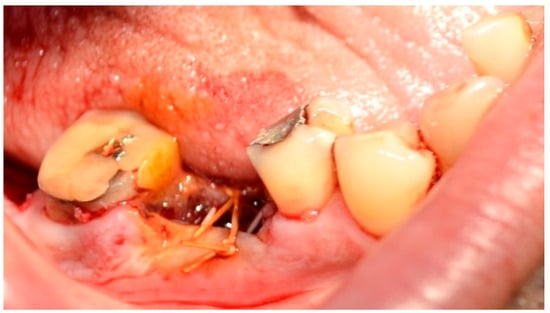

Autologous platelet concentrates (APCs), Figure 2, are biologically derived from a patient’s own blood, aimed at enhancing tissue healing and reducing inflammation. They contain a concentrated dose of platelets and growth factors that promote wound healing, tissue regeneration, and hemostasis [51].

Figure 2. A-PRF clot in glass-coated plastic tubes. Reprinted from Ref. [51].